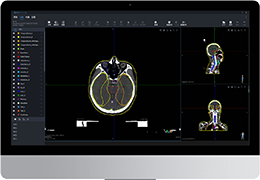

ART-Plan™ Artificial Intelligence Contouring